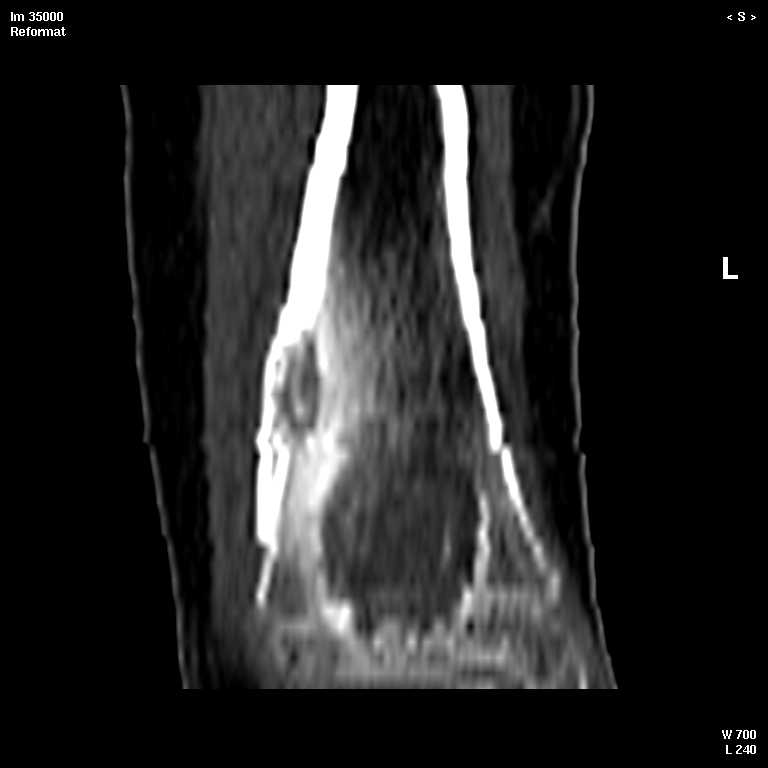

КТ изображения передаю на мой взгляд самые демонстративные. Их любезно записал коллега,

проводивший исследование в другом городе.

Прошу прощения за немного некоректную отправку КТ-снимков но по другому не получается :)